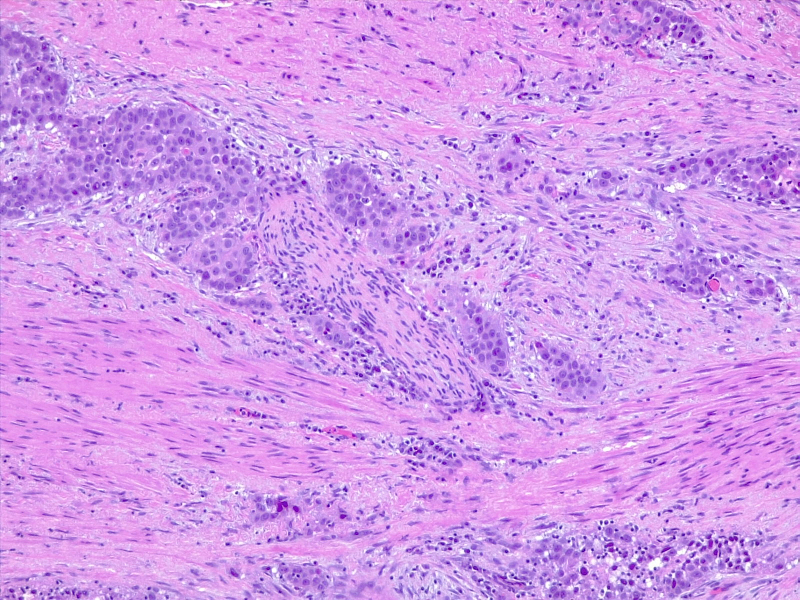

图3: 分化差的尿路上皮癌,具有化生性鳞状外观。10x,H/E。医学博士 Fabiola Farci 供稿